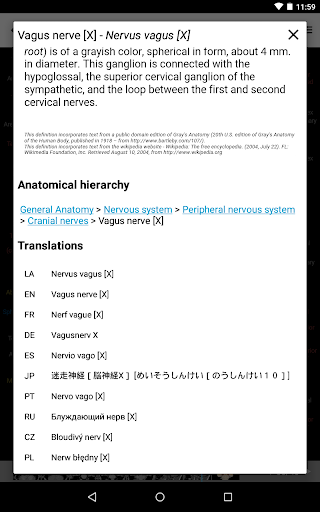

*Browse between anatomical parts using description links

-In the details view of an anatomical structure related terms are now displayed